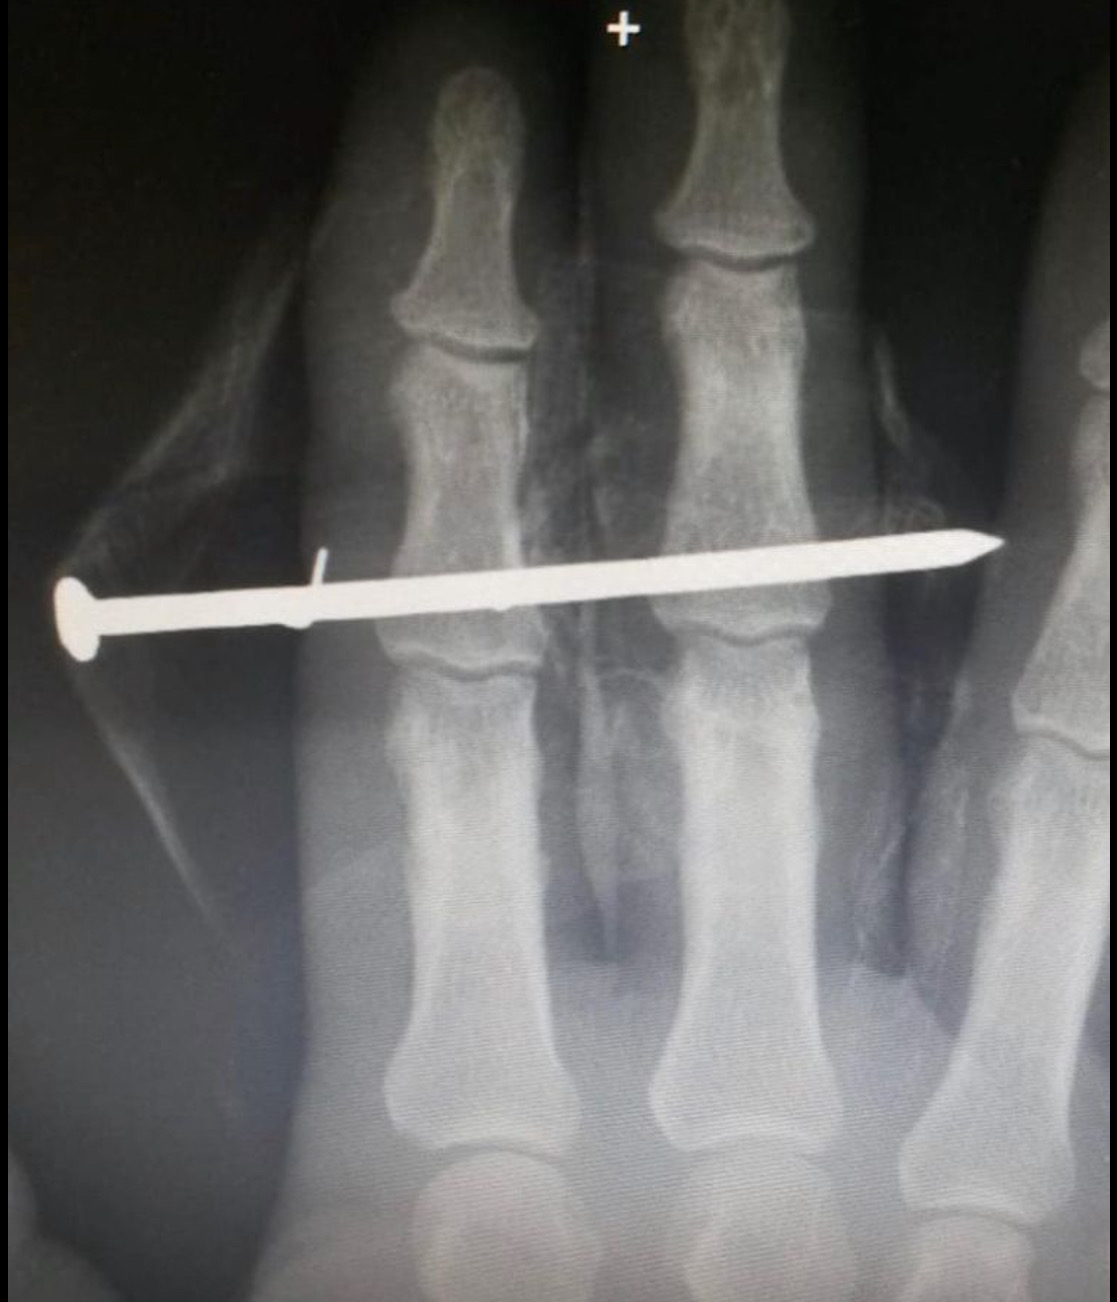

To build on the fundamentals of diagnostic imaging interpretation and knowledge of pathological conditions to include trauma of the spine and extremities, osteomyelitis, hematologic and vascular disorders.